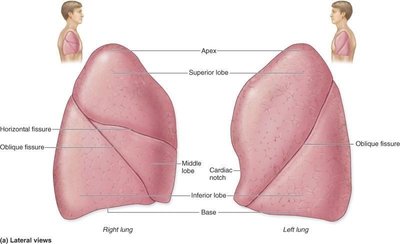

Lung Anatomy

The lungs are divided into lobes and segments, each supplied by its own bronchus and blood vessels. The right lung has three lobes; the left lung has two and a cardiac notch.

Bronchopulmonary Segments: Functionally independent units of the lung.

Pleurae: Double-layered serous membranes (parietal and visceral) that reduce friction and compartmentalize the lungs.